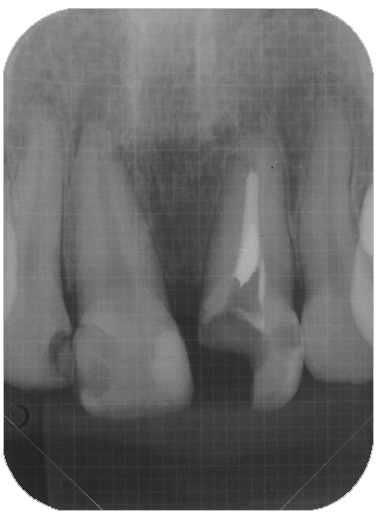

この組み合わせ3枚の写真はCT画像です。左の写真と真ん中の写真は同じものですが、わかりやすいように色を付けています。

黄色の線は根の外形です。

オレンジ色は、過去の根管治療の不備によりできた骨が吸収してしまった部分です。

赤の点線は、病変により破壊されてしまった上顎洞底(上顎洞と口の中を隔てる骨)の骨です。

水色は、それによって肥厚(腫れあがった)してしまった上顎洞粘膜です。

このような状態は2次元のレントゲンでは診断すらできません。CTを撮影することにより正確に診断ができ、それにあった処置法を選択する事が可能になります。

一番右の写真は処置直後で、MTAを用いて根管充塡し、治癒を待ちます。